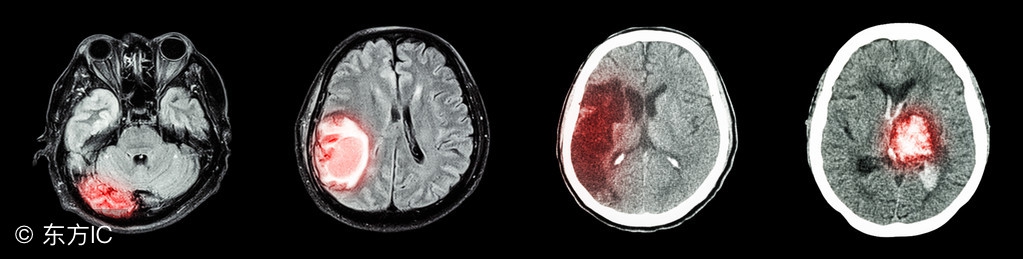

脑梗塞和脑溢血发病时的症状

脑堵塞发病时会产生偏瘫半身不遂、肢体麻木、偏盲、失语的症状。有时候也会产生语言障碍,而且还会造成记忆力下降的现象发生。很多的脑堵塞的患者还有口眼歪的症状。而脑溢血产生多是在情绪比较激动的情况下发生的。脑出血发病比急,可能在几个小时内就会造成患者的死亡。脑出血在发病前一般是没有什么先兆的。

脑出血病人发病后常有头痛,呕吐,血压高的现象,一些患者也会出现一些意识上在的障碍现象。还有比较简单的观察方法就是,脑出血的患者在发病的时候,眼部会有比较大的变化。有些患者会出现双瞳孔缩小和眼球同向偏视的现象。所以当身边的人突然的出现以上这些症状的时候要引起重视,应该马上让病人平躺下来打120或者是直接送医院,避免错过最佳的治疗时间。